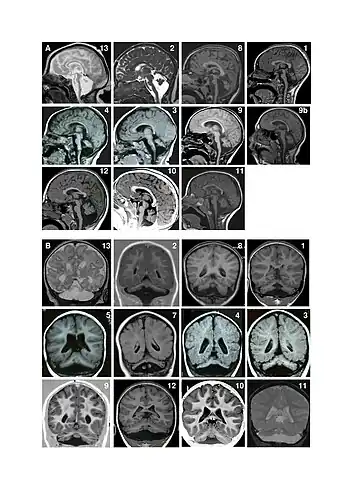

Facial features (dysmorphism) of patients with one form of pontocerebellar hypoplasia due to mutations in the CASK gene. A and B: patient at 1 year (A) and 4 years (B). C: patient, 18 months. D: patient, 13 years. E: patient, 13 years. F: patient, 12 years. Note minor facial dysmorphism: round face, small chin, well-drawn eyebrows in the younger patients; longer face, high and large nasal bridge, long nose, protruding maxilla, in the older patients. Magnetic resonance imaging (MRI) examples of patients with pontocerebellar hypoplasia with CASK mutations. A. Sagittal images showing different degrees of hypoplasia (incomplete formation) of the pons and vermis (parts of the brain). Numbers represent different patients. Figure 9a shows an MRI of a patient at age 4 months and figure 9b shows the same patient at age 11 years. There is no progression of the lesions between successive MRI in patient 9. Note that in all patients, the pons is very small but has a relative sparing of its bulging, mainly in its superior part. Hypoplasia predominates at the lower part of the pons. Vermis hypoplasia is very variable, severe in patient 13, very slight in patient 10-11-12 and also predominates at the inferior part. B. Coronal images showing varying degrees of cerebellar hemispheric (one of two halves of a part of the brain) hypoplasia. Hemispheres are frequently asymmetric. Note that the vermis does not protrude from the hemispheres indicating similar involvement of the vermis and the hemispheres. This pattern is different from that of PCH2 in which the vermis is relatively spared leading to the classic image of a "dragonfly", the protruding vermis being the body of the dragonfly and the hemispheres, the wings.

Magnetic resonance imaging (MRI) examples of patients with pontocerebellar hypoplasia with CASK mutations. A. Sagittal images showing different degrees of hypoplasia (incomplete formation) of the pons and vermis (parts of the brain). Numbers represent different patients. Figure 9a shows an MRI of a patient at age 4 months and figure 9b shows the same patient at age 11 years. There is no progression of the lesions between successive MRI in patient 9. Note that in all patients, the pons is very small but has a relative sparing of its bulging, mainly in its superior part. Hypoplasia predominates at the lower part of the pons. Vermis hypoplasia is very variable, severe in patient 13, very slight in patient 10-11-12 and also predominates at the inferior part. B. Coronal images showing varying degrees of cerebellar hemispheric (one of two halves of a part of the brain) hypoplasia. Hemispheres are frequently asymmetric. Note that the vermis does not protrude from the hemispheres indicating similar involvement of the vermis and the hemispheres. This pattern is different from that of PCH2 in which the vermis is relatively spared leading to the classic image of a "dragonfly", the protruding vermis being the body of the dragonfly and the hemispheres, the wings.